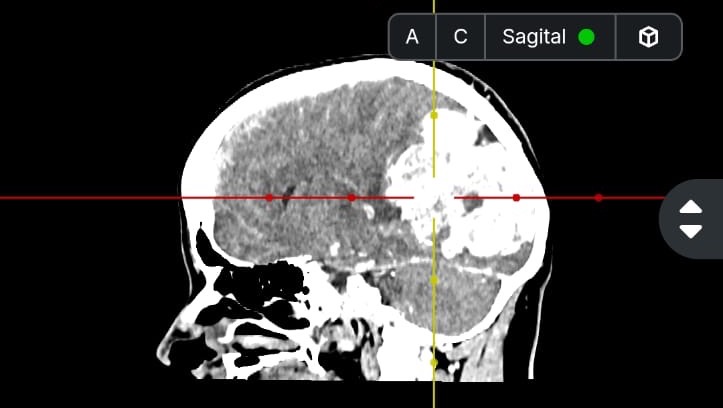

Hola me llamo Lucia del Carmen Morales Auvert tengo 38 años y estoy recaudando fondos ya que tengo que ser intervenida de emergencia debido a un proceso expansivo intracerebral y no cuento con los recursos necesarios para cubrir dicha operación, a su vez tengo que realizarme una Angiografia, gastos médicos y gastos quirúrgicos.

En este momento me van a realizar una embolizacion. Es un procedimiento para tratar vasos sanguíneos anormales en el cerebro y otras partes del cuerpo. Este procedimiento interrumpe el riego sanguíneo a cierta parte del cuerpo. Para después realizar la cirugía